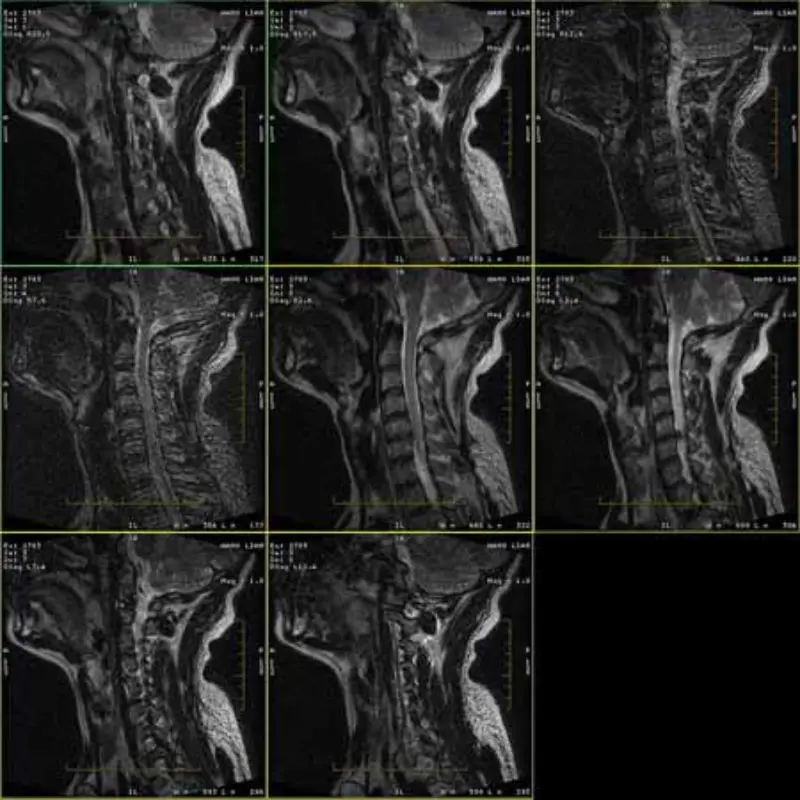

Obrazy protokołów FRFSE i GRE zawierają duchy i czasami obrazy o niskim współczynniku SNR pojawiają się w jednej serii. Ale obrazy protokołu SE są normalne.

Proszę spojrzeć na załączone obrazy.